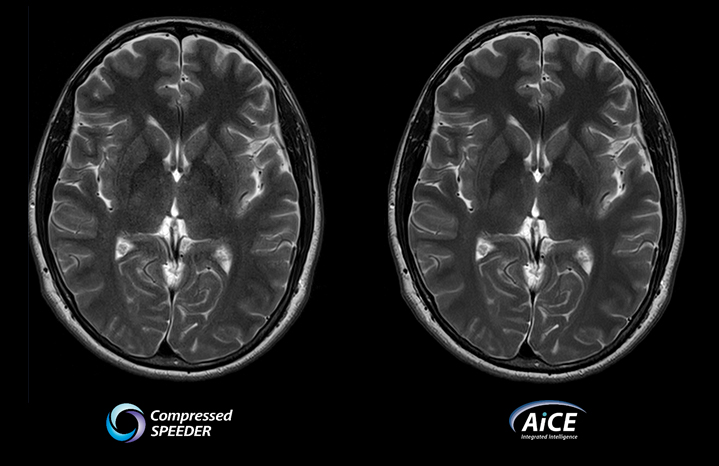

Совместите Compressed SPEEDER с AiCE DLR

- Увеличивайте разрешение за разумное время сканирования

- Улучшено качество изображения

- Повышенная клиническая уверенность

- Гибкость адаптации приобретения к текущей клинической задаче

- Увеличьте скорость или увеличьте отношение сигнал-шум и увеличьте разрешение

Время сканирования 2:00

из Vantage Galan 3T